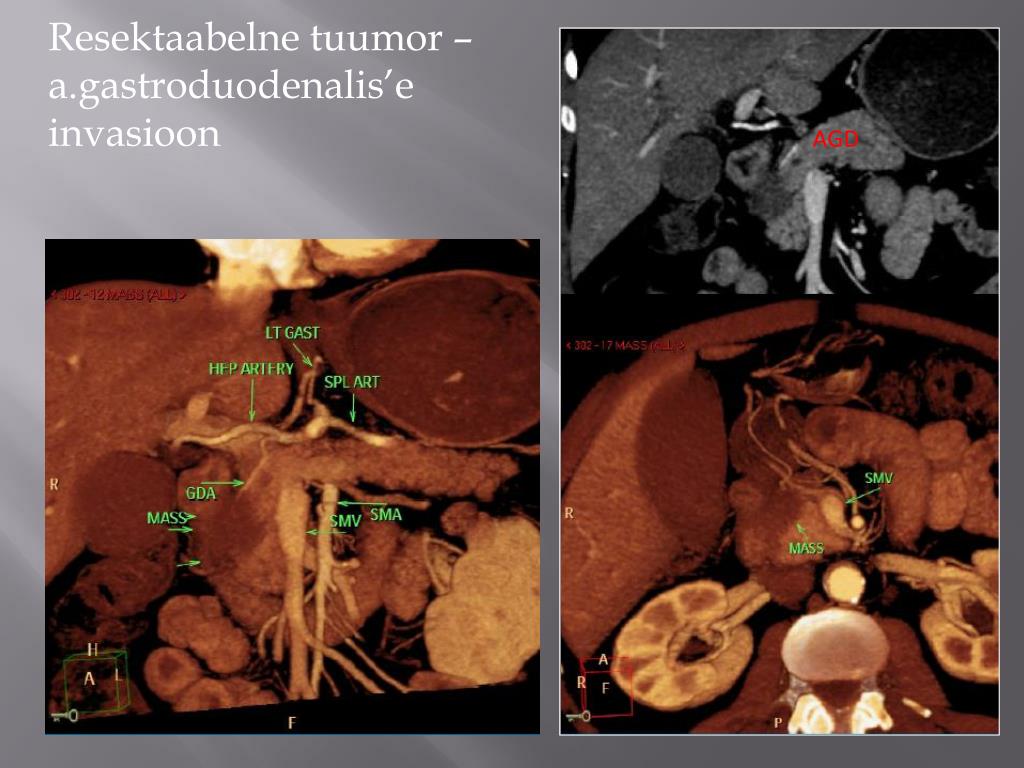

22. Arteriaalne invasioon • uuritakse tr. coeliacus, a. hepatica, a. mesenterica sup. • Tr. coeliacus`e, a. hepatica ja AMS`e invasioon on absoluutne vastunäidustus op. raviks (isegi < 50% veresoone ümbermõõdust). • A. gastroduodenalis`e invasiooni ei peeta vastunäidustuseks kiruurgiliseks raviks.

26. AGD Resektaabelne tuumor –a.gastroduodenalis’e invasioon